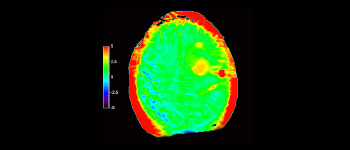

Astrozytom image

Astrozytom im Gehirn, nach Strahlentherapie

mit 3D APT